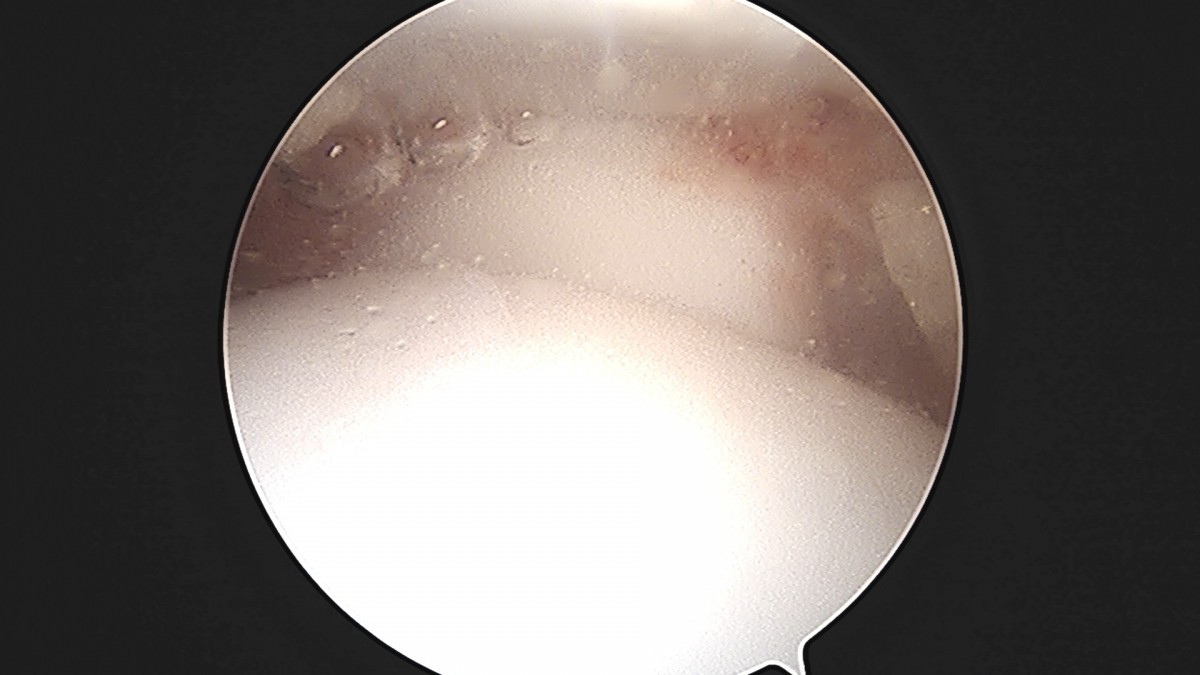

정지영원장님 발목 인대 봉합술 채이O 환자

작성자 최고관리자 댓글 0건 조회 718회 작성일 25-09-16 17:02